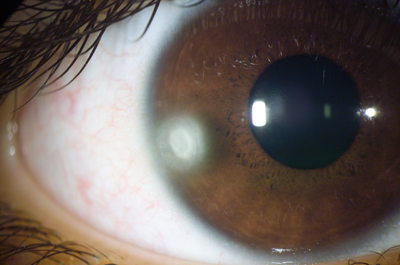

Descompensación de la Córneal Primaria

Distrofia Endotelial de Fuchs, conocida como córnea Guttata por el aspecto de las verrugosidades que aparecen en el endotelio. Con retroiluminación, (reflejo rojo) el aspecto endotelial es el de la plata martillada. Es una entidad familiar hereditaria y progresiva pero que toma décadas para desarrollarse. Produce pérdida de la transparencia de la córnea por incapacidad del Endotelio para mantener el estado de deshidratación corneal.

Los signos y los síntomas de la distrofia se hacen evidentes después de los 50 años con visión borrosa mayor al despertarce que mejora a lo largo del día. A medida que progresa, los periodos de emborronamiento se van haciendo más largos y permanentes.

Descompenzación Corneal

Descompenzación Corneal